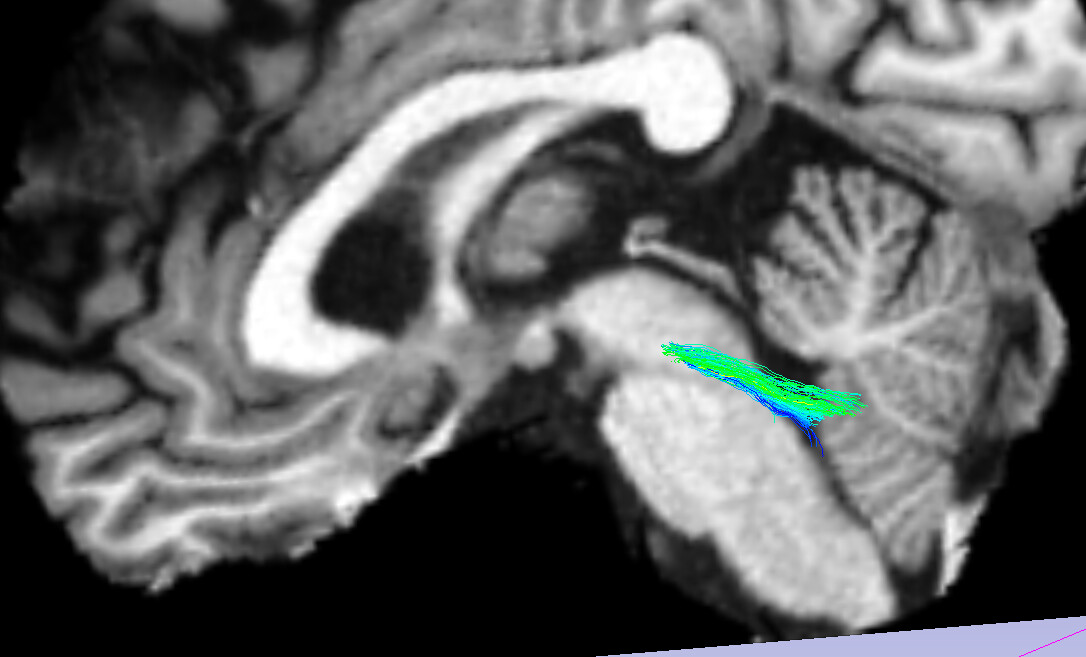

Given that the tool I use to extract the bundles is almost exclusively tested on VTK data, and does not accept TCK files, I am converting the TCK files to VTK using tckconvert ${in_fname} ${out_fname}. When I load the T1 and the resulting VTK file into 3D Slicer, streamlines land in the appropriate locations, so I assume things are OK there: